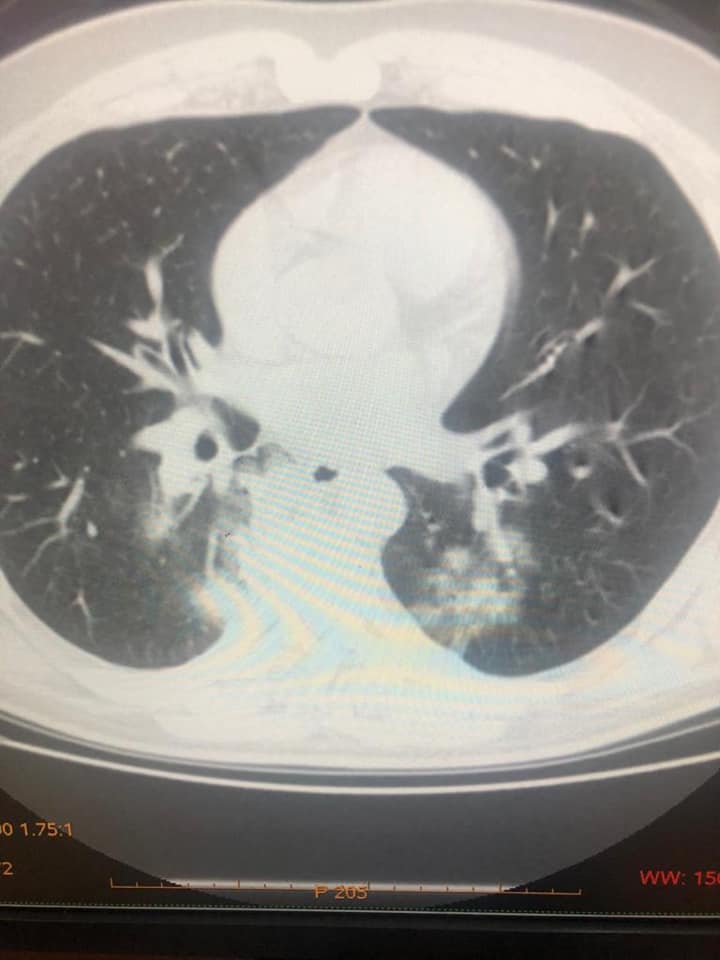

IMAZHET E JANARIT QË FLASIN PËR PREZENCËN E COVID-19 NË SHQIPËRI QË NË KËTË PERIUDHË

Sot, falë mikut dhe kolegut tim të nderuar Dr. Renato Osmani…, imazhëristit që ishte i pari, që javën e parë pas zbulimit të të ashtuquajturit rast 0, identifikoi fizionominë dhe identitetin imazhërik pulmonar të COVID-19… dhe potencën e ekzaminimit CT ndër ekzaminimet e skemës bazë për diagnostikim dhe përcaktim prognose…, mu ofruan imazhe të pakundërshtueshme të prezencës së COVID-19 në datat 15 – 20 janar, në disa raste në Infektiv…!!!

Faleminderit Dr. Renato…, jo vetëm për menaxhimin pa panik, por me vigjilencë të situatës së karantinës, nëpërmjet centarlizimit dhe koordinimit nacional imazhërik për suspektim sa më të hershëm të sëmundjes dhe prevenimin e kaosit, që mund të kish shkaktuar strategjia e gabuar e numrit 127…, por edhe për ndihmën që po jep për Komitetin Teknik për konfuzionin në pritjen e pikut epidemiologjik…!!! Po ju ofroj pamjet imazhërike të pesë rasteve, duke ju kujtuar që janë pronë intelektuale e Dr. Renato Osmani dhe i publikoj me aprovimin e tij, duke mbrojtur të drejtën e tij të aitorit…!!!